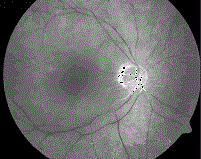

问题 患者,女性,60岁,高血压病史20年。2小时前突发左眼视力丧失,自诉似“电灯开关关闭”。眼底检查。 (如图)最可能的诊断是 ( )

选项 A、视网膜中央静脉栓塞 B、视网膜血管炎 C、急性球后视神经炎 D、颅内肿瘤 E、视网膜中央动脉栓塞

答案 E